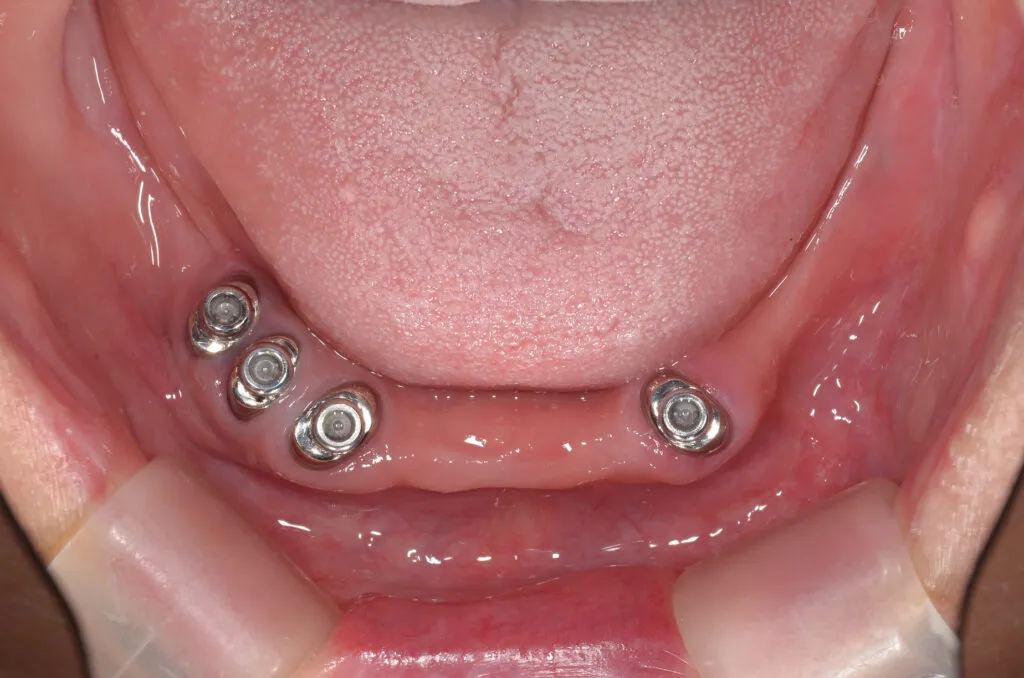

こちらの患者様の場合

【期間】2ヶ月

【費用】¥350,000~¥450,000/片顎(税抜)

【デメリット】精密に製作するため、保険の入れ歯よりも回数・費用がかかります。

上の写真は当院で上下総義歯を作製された患者さんです